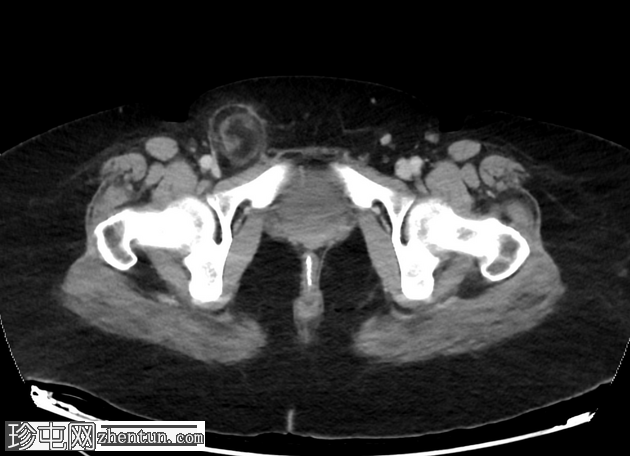

矢状C+门静脉期

右腹股沟疝,内含脂肪。疝颈位于下腹壁动脉起点下方。疝囊压迫股总静脉。脂肪含量不均质,脂肪条带状排列,并有微量液体,提示为嵌顿性股疝。

病例讨论

影像学特征符合右股疝,术中确诊,并采用腹腔镜联合开放手术(混合技术)进行右股疝修补术,使用网片进行修补。